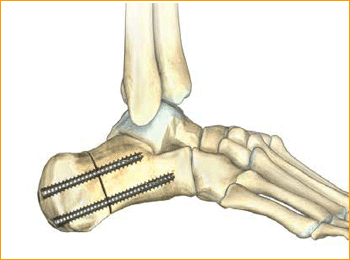

Jones Fracture Technique for 4.5 mm and 5.5 mm Headless Compression screws.

Calcaneal Osteotomy Technique for 6.5 mm Headless Compression screws.